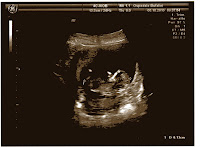

... our little Francis! About two weeks ago it was 6.13 cm, now I wonder, will definitely be bigger!

Having done the CVS, I already know the sex, though he is 13 weeks and some day.

In fact, here's what Francis gave to his father for having guessed before anyone else, her sex: D